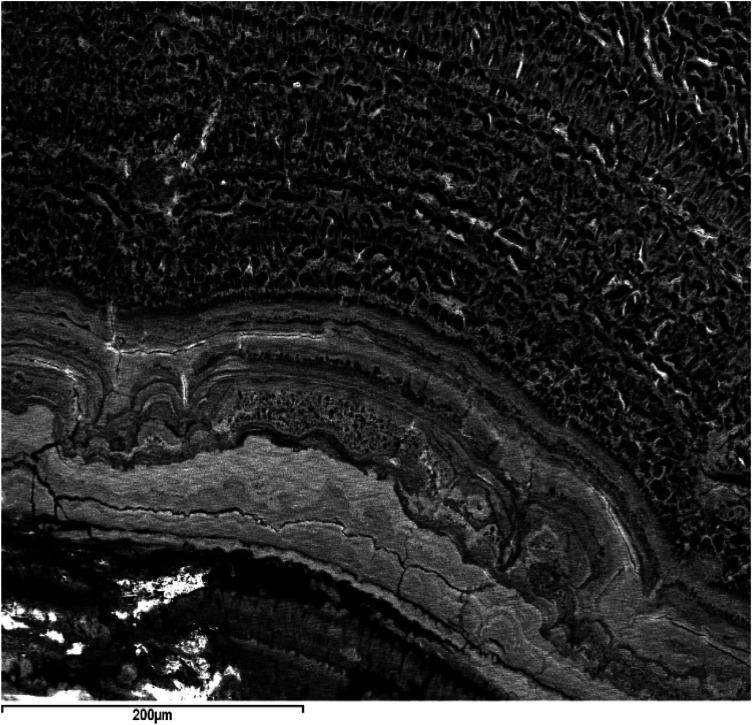

Salivary stones, or sialoliths, are calcified concretions forming within salivary glands and their ducts through a two-stage process: an initial formation of a central core via precipitation of inorganic material mediated by organic substances, followed by layering of additional organic and inorganic material. Substrates for sialolith formation include mucoid agglomerates, organic vesicles, foreign bodies, and bacterial biofilms. Understanding the detailed structure of sialoliths may aid in developing specific preventive or therapeutic strategies.

Most sialoliths were from the submandibular gland (82%), with the remainder from the parotid gland (18%). Parotid stones predominantly exhibited irregular shapes, while submandibular stones were generally ellipsoidal. All stones demonstrated an oolitic structure characterized by a central core surrounded by concentric layers and frequently associated with bacteria. Mineral composition predominantly included octacalcium phosphate (OCP), hydroxyapatite, and whitlockite. Larger sialoliths exhibited a higher proportion of hydroxyapatite, indicating increased crystallinity compared to OCP.

Despite diverse origins and locations, sialoliths share common morphological and compositional traits. Their formation begins with heterogeneous nucleation of calcium phosphates around organic spherules, likely induced by bacterial biofilms. These initial nuclei aggregate into a central core upon which additional layers of organic and inorganic materials deposit progressively. This layering increases the size and crystallinity of the sialoliths over time. The coexistence of amorphous phases and structural heterogeneity within layers explains the variability among stones. Detailed SEM-EDX analysis supports a unified conformational model for sialoliths that integrates the interplay of organic substrates, inorganic minerals, bacterial biofilms, and temporal factors.

Sialoliths are oolitic aggregates featuring a central core surrounded by concentric layers composed of organic and inorganic materials. Their formation process involves initial heterogeneous nucleation, bacterial influence, and progressive crystallization. This universal conformational model effectively describes sialolith formation irrespective of patient-specific or anatomical variations.

涎石,即唾液腺结石,是在唾液腺及其导管内通过两个阶段形成的钙化凝块:首先通过有机物质介导的无机物质沉淀形成一个中心核,随后是额外的有机和无机物质分层堆积。涎石形成的底物包括黏液样聚集体、有机小泡、异物和细菌生物膜。了解涎石的详细结构可能有助于制定特定的预防或治疗策略。

大多数涎石来自下颌下腺(82%),其余来自腮腺(18%)。腮腺结石主要呈不规则形状,而下颌下结石通常为椭圆形。所有结石均表现出鲕状结构,其特征是有一个被同心层包围的中心核,且常与细菌相关。矿物质成分主要包括磷酸八钙(OCP)、羟基磷灰石和白磷钙矿。较大的涎石中羟基磷灰石的比例更高,表明与OCP相比结晶度增加。

尽管涎石的起源和位置各不相同,但它们具有共同的形态和成分特征。它们的形成始于围绕有机小球的磷酸钙异质成核,可能由细菌生物膜诱导。这些初始核聚集成一个中心核,在其上有机和无机材料的额外层逐渐沉积。随着时间的推移,这种分层增加了涎石的大小和结晶度。层内非晶相和结构异质性的共存解释了结石之间的变异性。详细的SEM-EDX分析支持了一个统一的涎石构象模型,该模型整合了有机底物、无机矿物质、细菌生物膜和时间因素之间的相互作用。

涎石是鲕状聚集体,具有由有机和无机材料组成的同心层包围的中心核。它们的形成过程涉及初始异质成核、细菌影响和渐进结晶。这个通用的构象模型有效地描述了涎石的形成,而不考虑患者特异性或解剖学变异。